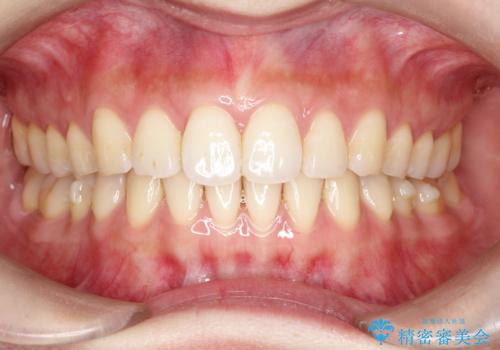

【八重歯・がたつきでお悩みの方必見】抜歯矯正症例(審美ワイヤー矯正)

担当医 奥村高広